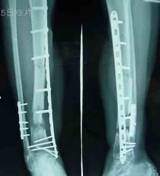

在胫骨骨不连平面的近端,截断腓骨,将腓骨近端与胫骨骨不连平面的近端胫骨紧密接触,用2枚螺丝钉固定,结合部位髂骨松质骨植骨。将截除腓骨2.5cm,植入胫骨骨不连骨缺损部位,再用髂骨松质骨植骨,修复骨缺损。

手术后15个月,骨不连已经愈合,患者可以部分负重行走。